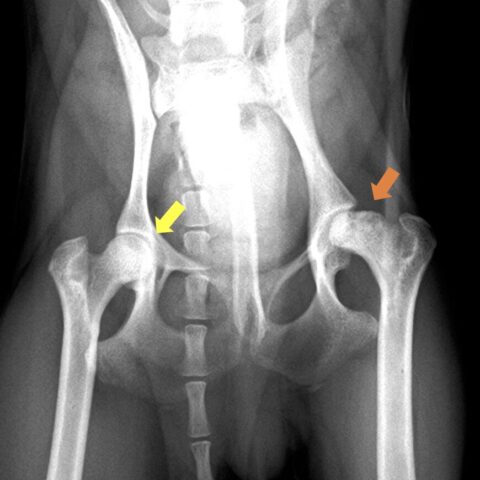

黄色矢印:正常な大腿骨頭、オレンジ矢印:大腿骨頭壊死症に罹患しており、骨吸収と変形を認める。